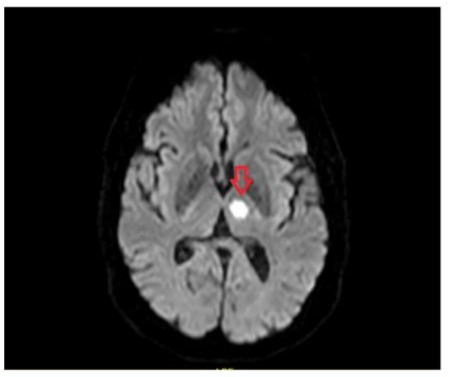

Patient was treated with standard stroke care which included anti-platelet therapy, statins and multi-disciplinary (MDT) approach. The MDT included stroke physicians, rheumatologists, radiologists, speech and language therapists, physiotherapists and occupational therapists. An MRI scan with DWI FLAIR imaging of the brain was arranged (figure 2) to determine the age of the infarct, the MRI confirmed an acute stroke in the left thalamus. A 24-hour tape was arranged to observe electrical activity of the heart which did not reveal any arrythmias. Carotid ultrasound was normal. A referral was also made to Rheumatology team to advise further on PACNS management. They did not advise any further change in medication. The view of MDT was that this stroke was a likely complication of PACNS.

Figure 2: Well-defined focal area (red arrow) of FLAIR hyperintensity involving the left thalamic region signifying an acute infarct on the MRI DWI FLAIR scan.